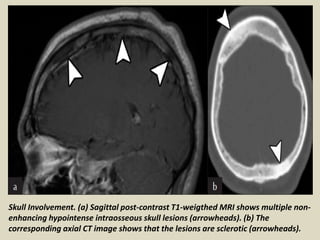

Skull Involvement. (a) Sagittal post-contrast T1-weigthed MRI shows multiple non-

enhancing hypointense intraosseous skull lesions (arrowheads). (b) The

corresponding axial CT image shows that the lesions are sclerotic (arrowheads).